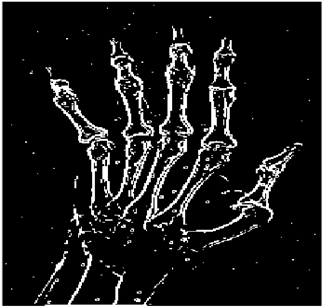

Table 5. X-ray Images.

X-ray 1X-ray 2X-ray 3X-ray 4X-ray 5

Mathematics 10 02421 i004 Mathematics 10 02421 i005 Mathematics 10 02421 i006 Mathematics 10 02421 i007 Mathematics 10 02421 i008

For the purpose of simulation, we consider two sets of images: (1) three images from MATLAB repository (Table 4) and (2) five X-ray images available online (Table 5).